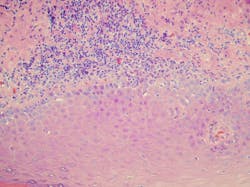

One of the theories behind LPP is that it initially starts as lichen planus. As the proteins from the basement membrane region become increasingly exposed as a result of chronic inflammation and damage, autoantibodies develop against one of these proteins (figures 2, 3).

A diagnosis is confirmed through a biopsy and the use of clinicopathologic correlation. The biopsy results are used to differentiate the above mentioned entities.3,4 With any of the skin diseases mentioned here, it is crucial to get a definitive diagnosis through a biopsy and adjunct immunofluorescence for confirmation.